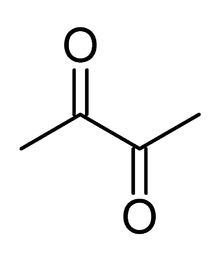

Diacetyl

Bronchiolitis obliterans may be caused by inhalation of airborne diacetyl, a chemical used to produce the artificial butter flavoring[15] in many foods such as candy and microwave popcorn and occurring naturally in wines. This first came to public attention when eight former employees of the Gilster-Mary Lee popcorn plant in Jasper, Missouri, developed bronchiolitis obliterans. In 2000, the Missouri Department of Health called in the National Institute for Occupational Safety and Health to make a determination of the cause, and to recommend safety measures. After surveying the plant and each patient's medical history, NIOSH recommended respiratory protection for all workers in microwave popcorn production. Due to this event, bronchiolitis obliterans began to be referred to in the popular media as "popcorn Lung" or "popcorn workers lung".[16][17][18][19] It is also referred to as "flavorings-related lung disease".[20]

Bronchiolitis obliterans caused by diacetyl inhalation begins with a cough, wheezing and dyspnea (shortness of breath), and usually progresses slowly, but severe symptoms can develop without warning. Other symptoms that appear in some workers include fever, weight loss, and night sweats. Symptoms do not change when workers are away from the workplace.[20] CT images show bronchial wall thickening and trapped air. Non-smokers may be at higher risk for this form of bronchiolitis obliterans. The Occupational Safety and Health Administration (OSHA) recommended that diacetyl manufacturing companies regularly sample air in work environments, provide air purifying respirators, and engage in medical surveillance of at-risk workers. In 2011, National Institute for Occupational Safety and Health proposed a recommended short-term exposure limit of 25 parts per billion (ppb) and a time weighted average exposure of 5 ppb.[19]

Diacetyl is approved by the Food and Drug Administration as a safe flavor ingredient, but there is evidence to suggest that inhalation in large amounts is dangerous. There are currently no warnings from federal regulators about diacetyl.

A NIOSH peer-reviewed publication documents that, in laboratory studies, acute inhalation exposures to acetyl propionyl(2,3-pentanedione), one of the compounds with a buttery flavor and/or smell put forward as a safer alternative to diacetyl, cause airway epithelial damage that is as harmful as diacetyl.[30]